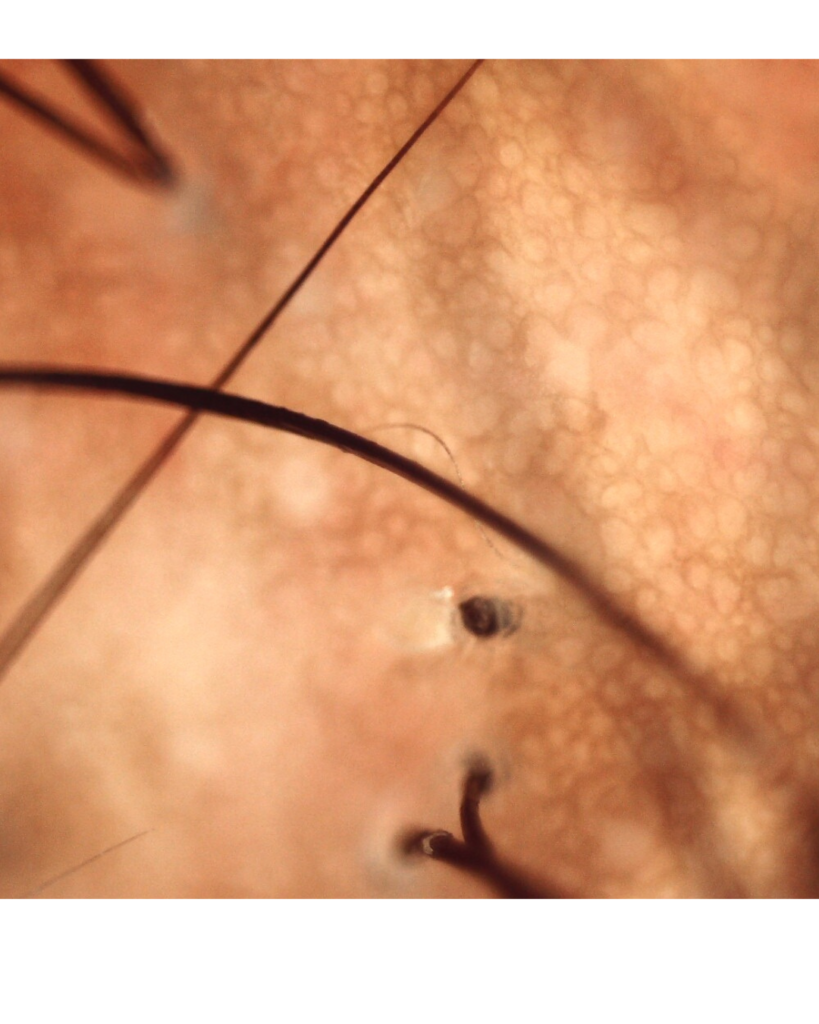

Abaixo vemos duas imagens de tricoscopia em cabelo cacheado com alopecia por tração.

A avaliação com tricoscopia ou dermatoscopia pode auxiliar no diagnóstico diferencial. Um profissional Dermatologista , Tricologista ou um técnico em Terapia Capilar podem te auxiliar a identificar e tratar os sinais da alopecia por tração. A detecção precoce é decisiva para a reversão.